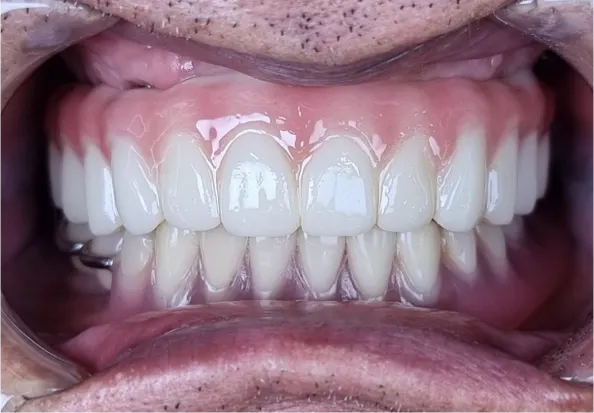

최종 보철물 연결 (2024.02.29)